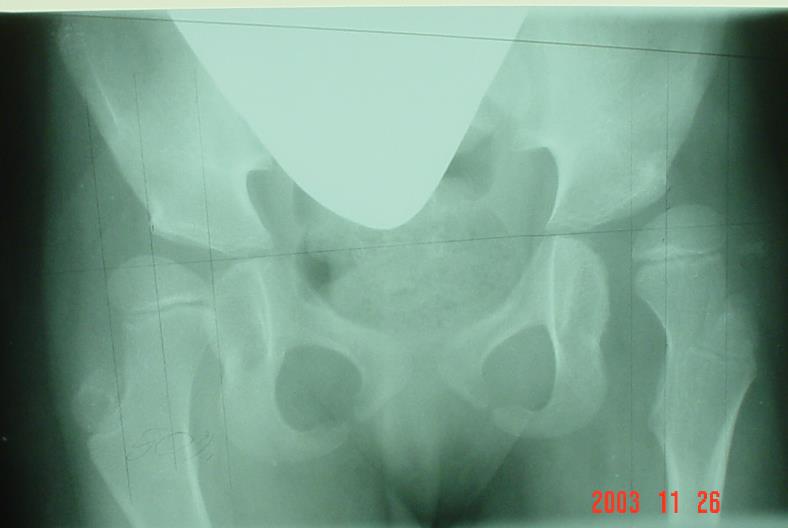

Załączony radiogram przedstawia stawy biodrowe dziecka w wieku 9 lat z mózgowym porażeniem dziecięcym typu tetraplegii spastycznej, GMFCS V. Właściwa decyzja lecznicza to:

Pytanie 98